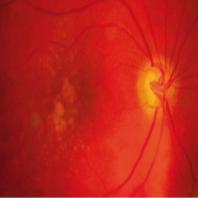

- eCas clinique 13-1

- eCas clinique 13-2 enoncé

- eCas clinique 13-2A

- eCas clinique 13-2B

- eCas clinique 13-2C

- eCas clinique 13-2D

- eCas clinique 13-2E

- eCas clinique 13-2F

- eCas clinique 13-2G

- eCas clinique 13-2H

- eCas clinique 13-2I

- eCas clinique 13-2J

- eCas clinique 13-2K

- eCas clinique 13-2L

- eCas clinique 13-2M

- eCas clinique 13-2N

- eCas clinique 13-2conclusion

- eCas clinique 13-3enoncé

- eCas clinique 13-3A

- eCas clinique 13-3B

- eCas clinique 13-3C

- eCas clinique 13-3D

- eCas clinique 13-3E

- eCas clinique 13-3F

- eCas clinique 13-3G

- eCas clinique 13-3H

- eCas clinique 13-3I

- eCas clinique 13-3J

- eCas clinique 13-3conclusion

- eCas clinique 13-4enoncé

- eCas clinique 13-4A

- eCas clinique 13-4B

- eCas clinique 13-4C